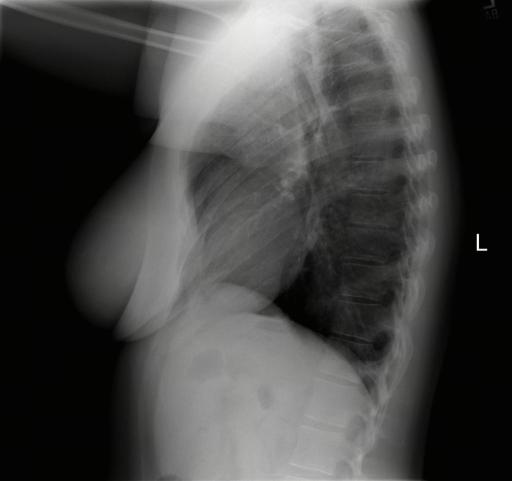

Public Dataset Integration for Breadth. We leverage established open-source datasets (e.g., MIMIC-CXR [28], CheXpert [24], and ROCO [47]) to provide a foundational layer of visual variety. These datasets offer a vast quantity of samples covering common pathologies and standard anatomical views. However, raw annotations in public datasets are often noisy or limited to binary classification tags (e.g., “Pneumonia: Positive”).

Stage 3: Multi-Granularity Instruction Formatting. To enable the model to handle various user intents, we do not simply pair the image with a single caption. Instead, we generate diverse instruction-response pairs derived from the generated caption. These include: (1) Descriptive Instructions (e.g. “Describe the findings in this chest X-ray.”), (2) Diagnostic Q&A (e.g. “Is there evidence of pleural effusion? If so, describe its location.”), (3) Localization Tasks (e.g. “Identify the region responsible for the patient’s shortness of breath.”), and (4) Reasoning Prompts (e.g. “Based on the visual evidence, what is the most likely diagnosis and what follow-up is recommended?”).

The training dataset is built mainly from radiology imaging data (e.g., X-rays, CT scans, MRI) and public de-identified radiology datasets, which include pathological/normal cases, metadata and expert annotations. Given the varying diagnostic complexity and tool utility of raw radiology data, a two-stage filtering pipeline is adopted to create an effective RL training set:

Medical report generation stresses long-form coherence and, more importantly, faithfulness: the ability to describe findings without introducing subtle hallucinations or unsupported claims. Evaluation in this category is particularly sensitive to protocol choices (e.g., what constitutes an omission versus an incorrect addition), which motivates our unified prompting, structured output requirements where applicable, and complementary inhouse faithfulness tests. Tab. 7 lists the report benchmarks included.